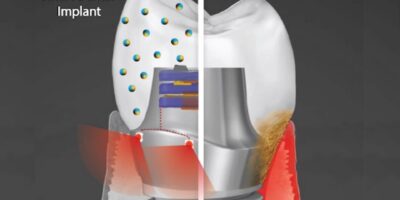

Geelsu Hwang of the School of Dental Medicine and colleagues are developing a smart dental implant that ...